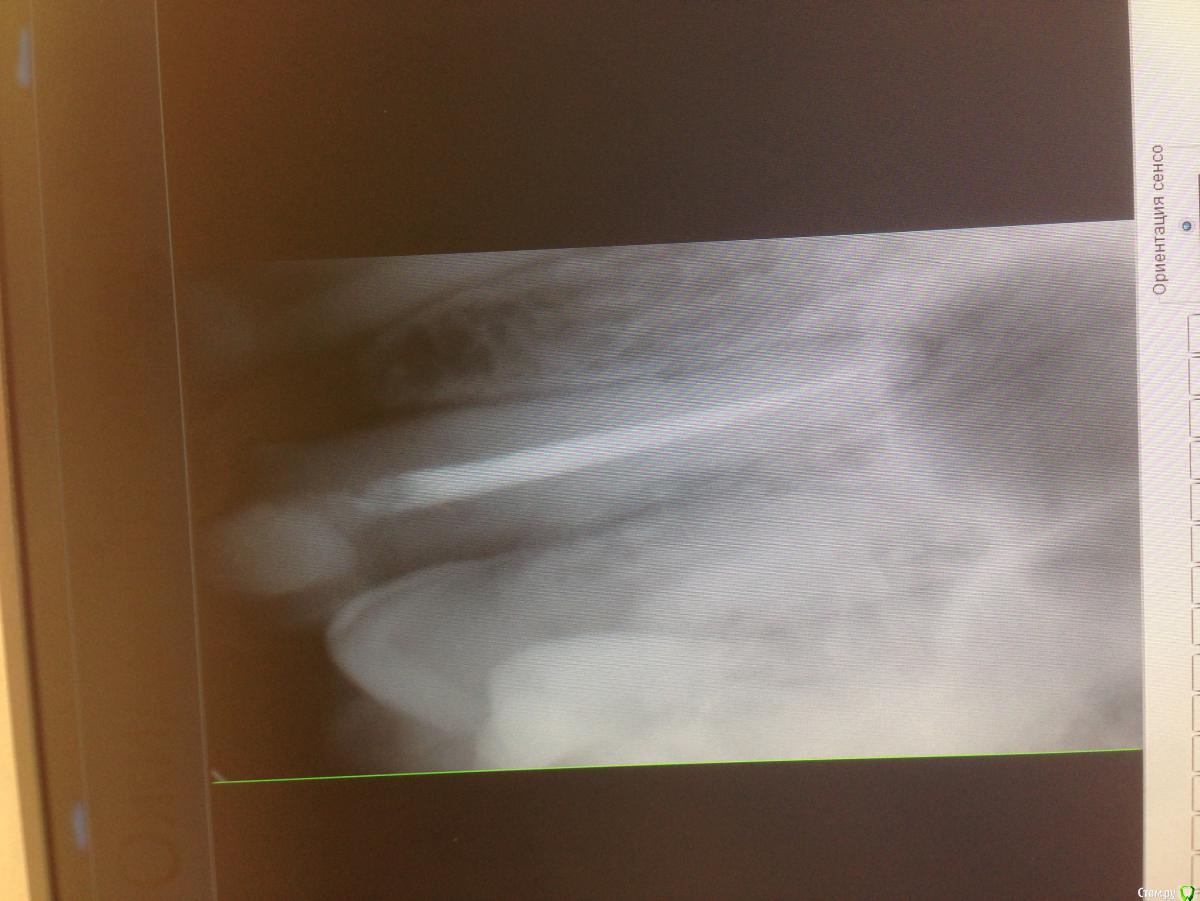

kos98 Опубликовано 24 февраля, 2016 Поделиться Опубликовано 24 февраля, 2016 (изменено) Добрый день. Имеется депульпированный ранее( года 4 назад) левый верхний клык. Недавно откололась порядка 50% зуба со внутренней стороны(может меньше). Было решено пойти к ортопеду для консультации по поводу установки коронки на данный зуб. Был сделан снимок, по его данным - все хорошо. Предложили сделать ревизию канала (чем наполнен, плотность итд) перед непосредственно первым этапом в протезировании. Скажите, пожалуйста, всегда ли ее делают? И есть ли смысл в сочетании кобальто-хромовая вкладка с циркониевой коронкой? Надежность?.. Снимки прикрепил.Спасибо. Изменено 24 февраля, 2016 пользователем kos98 Ссылка на комментарий

red_butler Опубликовано 24 февраля, 2016 Поделиться Опубликовано 24 февраля, 2016 Добрый день. Снимки прикрепил.Я бы вел речь не о ревизии, а сразу о повторном лечении корневого канала 1 Ссылка на комментарий

kos98 Опубликовано 24 февраля, 2016 Автор Поделиться Опубликовано 24 февраля, 2016 Я бы вел речь не о ревизии, а сразу о повторном лечении корневого каналаВ чем здесь видится проблема с пломбировкой? Ссылка на комментарий

red_butler Опубликовано 24 февраля, 2016 Поделиться Опубликовано 24 февраля, 2016 В чем здесь видится проблема с пломбировкой?Да и признаки воспаления. Ссылка на комментарий

IvanK Опубликовано 25 февраля, 2016 Поделиться Опубликовано 25 февраля, 2016 + к повторному лечению Ссылка на комментарий

M@estro Опубликовано 25 февраля, 2016 Поделиться Опубликовано 25 февраля, 2016 Перелечивать. Ссылка на комментарий

kos98 Опубликовано 25 февраля, 2016 Автор Поделиться Опубликовано 25 февраля, 2016 Благодарю за ответы. Подскажите, пожалуйста, по каким признакам на данном фото это видно?Из 3х клиник, только в одной предложили перелечивать. И еще к вопросу - КХС + Циркониевая коронка - имеет ли смысл в данном варианте? Или только Ц-ий+Ц-ий ? Ссылка на комментарий